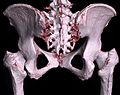

3D-Rekonstruktion (Volumenrendering) des Beckens aus einem CT-Scan -